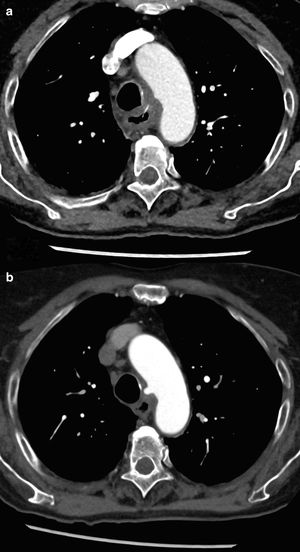

An 86-year-old woman with no medical history came to the emergency room due to dysphagia and shivering for 4 days after eating fish. Lab work-up: leukocytosis with left shift. Thoracic CT scan: esophageal circumferential thickening due to a foreign body associated with a small mediastinal hematoma, fatty reticulation and loss of fatty plane with the aortic arch (Fig. 1a); fishbone observed pointing towards the aortic arch (Fig. 2a). Diagnosis: esophageal perforation and suspected mediastinitis. Treatment: endoscopic extraction and conservative treatment. Follow-up CT scan: additional image in the aortic arch along the tract of the foreign body from previous CT scan (Fig. 1b). Diagnosis: aortic arch pseudoaneurysm (Fig. 2b). PET/CT scan: mediastinitis not ruled out. Treatment: antibiotic therapy for 2 weeks. Two-stage surgery: creation of space for non-fenestrated endovascular prosthesis, through right carotid subclavian transposition and aberrant right subclavian artery ligation; stent placement to exclude the pseudoaneurysm. No immediate postoperative complications were observed.